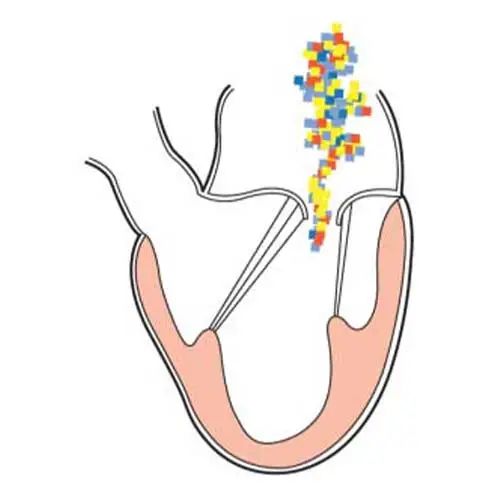

此培训为MAYO诊所推出的心内科fellow系列培训之一,主要目的是能够使大家学习到AMI以后心脏机械并发症的识别和诊断,还有ACS的非心脏的并发症的表现,以及临床中存在与ACS临床上有相似之处的非心脏疾病。 急性心肌梗死后出现的并发症,分为心脏性和非心脏性的,心脏并发症又包括心电学方面的并发症以及机械并发症,非心脏性并发症包括血栓栓塞和出血,还可能出现与心包相关的并发症。 心脏机械并发症包括就是破裂性和非破裂性的2类,破裂性并发症包括游离壁破裂、室间隔穿孔和乳头肌断裂,其中游离壁破裂既可能是直接的穿孔,也可以是亚急性破裂形成假性动脉瘤这样包容性的破裂。而非破裂性机械并发症包括严重的左室心力衰竭,右室梗塞,左室壁动脉瘤以及缺血性二尖瓣反流。 从根本上来说,这些严重并发症的发生都与心脏的泵功能衰竭有关,泵功能的衰竭造成了血流动力学不稳定以及基线的电不稳定性。 第一节:非破裂性机械并发症 非破裂性机械并发症,即严重的左室心力衰竭——心源性休克,右室梗塞,左室壁动脉瘤以及缺血性二尖瓣反流。 1、 心源性休克:在心梗发生时,发生心源性休克的主要原因就是大面积的心肌梗死,那么如果要导致心脏泵功能衰竭,左室心肌质量至少要损失40%以上。其他导致心源性休克的原因还有右室梗塞、心脏破裂以及快速和缓慢性心律失常。 2、 右室梗塞:也是导致心源性休克发生的重要原因。在下壁心梗的患者中,大概有33%的患者同时也发生右室梗死,这种情况多见于RCA近端闭塞,与高死亡风险相关。在所有下壁STEMI者中都要考虑是否同时存在RV梗塞,心电图V1和RV4导联ST段抬高超过1mm为其特异性心电图改变(图1)。 图1. 右室梗塞的心电图表现 3、 右室梗塞为什么会导致患者发生心源性休克呢?从病理生理上讲,右室急性缺血时会致其收缩不良,导致RV每搏输出量和峰压降低,继而是左室前负荷降低,心输出量降低;另一方面,急性缺血还同时使右室舒张功能受损,此时右心充盈压显著增加,并且由于右室急剧扩张,会在心包内占据很大体积,使得心包内压力显著增加,这些综合造成的结果使RV和LV的充盈减少。左心充盈压下降而右心压力不断升高,最终导致低血压、肺血流减少、颈静脉压升高,其临床结果可能类似于心包填塞以及缩窄性心包炎。 4、 左室壁动脉瘤(图2):首先提出一个问题供大家思考,以下有关左室壁动脉瘤的说法哪一个是正确的?1左室壁动脉瘤只局限于心内膜下;2有一个相对狭窄的颈部;3是否都与前壁心梗有关;以及4容易有血栓的附着,并且心包是组成瘤壁的一部分。实际上,左室壁动脉瘤在STEMI后的发生率<5%,前壁梗死的患者更易发生,及时进行再灌注治疗可以降低其发生率。它突出于心腔外侧,瘤壁就是左室壁,颈部和底部的比例大约是1:1,可以出现附壁血栓。所以上述说法中只有3是正确的。 图2. 左室壁动脉瘤示意图,O;颈部,D:底部,LA:左心房,LV:左心室,AO:主动脉 5、 缺血性二尖瓣反流:为心梗后左室重构所致,表现为乳头肌移位、乳头肌功能不良使瓣叶活动受限以及瓣环扩张(图3)。治疗的焦点集中于及时的再灌注治疗、利尿剂的应用和后负荷的降低,如果遗留严重的二尖瓣反流,则会导致心梗后的远期生存率下降。 图3. 瓣环扩张(A)、乳头肌功能不良致瓣叶活动受限(B)导致大量MR 第二节:破裂性机械并发症 破裂性并发症包括游离壁破裂、室间隔穿孔和乳头肌断裂,其中游离壁破裂既可能是直接的穿孔,也可以是亚急性破裂形成假性动脉瘤这样的包容性破裂。大多数破裂性并发症都发生在AMI的第一个24小时之内,剩余的则发生在1周之内。通过超声心动图可以发现MI的机械并发症,包括急性乳头肌断裂、下段室间隔断裂、上段室间隔断裂以及二尖瓣脱垂。 1、 乳头肌断裂所致二尖瓣反流(图4):乳头肌断裂常发生在MI后的2~7天,急性缺血事件发生时,从心外到心内的压力梯度增加,心内灌注降低,乳头肌属于心内结构,缺血的敏感性增加。一旦出现需要外科手术治疗。 图4. 乳头肌断裂(箭头所示) 2、 室间隔缺损(图5):属于MI后的罕见并发症,多于梗死后3~5天发生,在梗死后即刻或者第一个24小时内就可以发生,部分与患者进行的纤溶治疗有关。由于再灌注治疗的开展,目前发生率已经由2%降至0.2%。破裂发生在健康心肌和坏死心肌的交界处,在前壁心梗时,缺损位于室间隔心尖部,下壁心梗时缺损则位于下-后间隔基底段,RV梗死及功能失常者预后不良。 图5. 前壁心梗(A)、下壁心梗(B)所致不同部位室间隔穿孔 3、 游离壁破裂:急剧的、常为致死性机械并发症;发生率<1%;MI后死亡约8~24%是由此而造成;通常在梗死后的5天内发生。好发因素包括1首次心梗,2前壁心梗,3老年患者以及4女性。 4、 亚急性破裂:是一种特殊类型的游离壁破裂,占所有游离壁破裂患者的约1/3,是因为附壁血栓和心包覆盖了穿孔部位所致,局部表现为假性动脉瘤(图6),临床上常比较隐匿,并且可能仅通过UCG发现,因此任何超声发现的心脏周围局部积液都需要引起怀疑并详细扫查。与真性动脉瘤(即左室壁动脉瘤)不同,假性动脉瘤的颈部狭窄,颈部与底部的比值<0.5,心包是瘤壁的组成部分。亚急性破裂的进展常是难以预测,可以进展至完全破裂乃至心包填塞,因此需要外科治疗。 图6. 左室假性动脉瘤示意图,O;颈部,D:底部,LA:左心房,LV:左心室,AO:主动脉 第三节:AMI的非心脏并发症 AMI的非心脏并发症主要包括血栓栓塞和出血,以及心包并发症。那么下面关于左室血栓的说法哪个是正确的呢?1下壁心梗更为常见,2如果不予治疗栓塞风险可达50%,3栓塞的风险取决于血栓的移动性和是否凸出于腔内。左室血栓常(图7)见于大面积前壁心梗,在再灌注前时代其发生率可高达40%,有再灌注治疗后这一几率已降至4~15%;经胸超声心动图是发现LV血栓的第一选择;心脏MRI的敏感性更高,但与超声心动图的特异性相似。由于心梗后不运动和运动障碍的室壁区域存在静止血流,因此如容易在局部形成附壁血栓。如果梗死部位为心尖部,且左室EF值减低达<30%,则存在血栓栓塞的高风险。如果未治疗,左室血栓发生栓塞的风险为10~15%,这一风险的高低还取决于栓子的移动性和是否突出于心腔内,早期且持续的抗凝治疗(3~4个月)可以降低栓塞风险。 图7. 左室心尖部附壁血栓 一图总结心脏机械并发症 第四节:类似ACS的非心脏疾病 通过一个有趣的病例,我们来学习一下在临床中可能存在类似于ACS表现的非心脏疾病。这是一个77岁老年女性,症状为头晕、恶心、呕吐,急诊CT除外了急性卒中,但心肌坏死标记物升高,心电图提示为Af、并且下壁前壁导联T波倒置,但超声心动图上仅表现为室间隔中下段至左室心尖部运动减低,没有看到下壁及前壁的运动异常。随后患者出现严重的高血压和心动过缓,并存在定向力、消化不良和眼球震颤,继续监测头CT及MRI,结果发现枕叶大面积脑梗。实际上,早在1947年,急性卒中所引起的ECG变化就已经被报道,病程中出现深大的倒置T波则被称为神经源性T波。在急性颅内事件发生时可以存在肌钙蛋白的升高以及心电图出现ST-T改变,在卒中的急性期,ECG诊断急性心梗的特异性会降低。 除急性脑血管病以外,以下疾病也会出现类似于ACS的临床发现,包括心电图异常和心肌坏死标记物升高,如特发性应激性心肌病,主动脉夹层,肺栓塞等等,需要及时进行诊断及鉴别诊断。 最后需要强调的是,超声心动图是发现AMI后心脏机械并发症的最重要检查,AMI发生后一周内必须行UCG检查以发现隐匿的高危并发症。